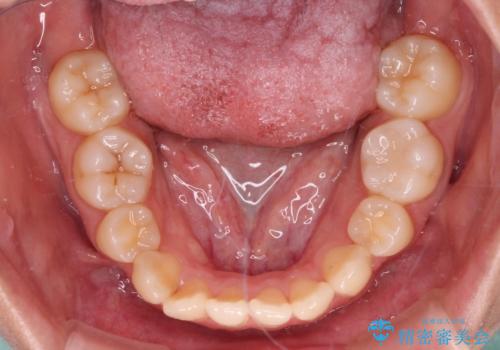

- 抜歯矯正の後戻りを気にして来院された患者様です。

舌の突出癖によるオープンバイトになっていたため、インビザラインによるマウスピース矯正をおすすめしましたが、自己管理の自信がないとのことで、ワイヤー装置による矯正治療を行うこととしました。

舌の突出癖が認められると、上下前歯の隙間を閉じることができません。

舌のトレーニングをしっかりと行っていただくことで、歯列を整えることができます。